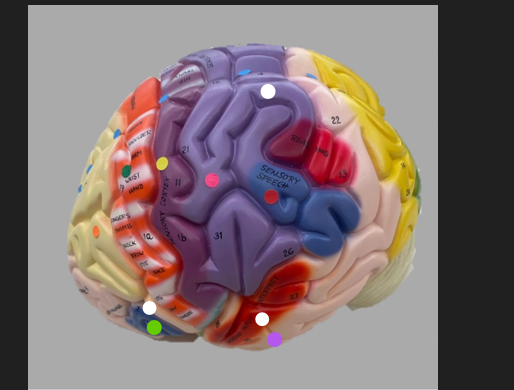

orange dot

frontal lobe

blue dot

longitudinal fissure

dark green dot

precentral gyrus

pink dot

postcentral gyrus

yellow dot

central sulcus

white dot

parietal lobe

light green dot

Broca’s Area

red dot

Wernicke’s Area

orange dot

occipital lobe

blue dot

parieto-occipital sulcus